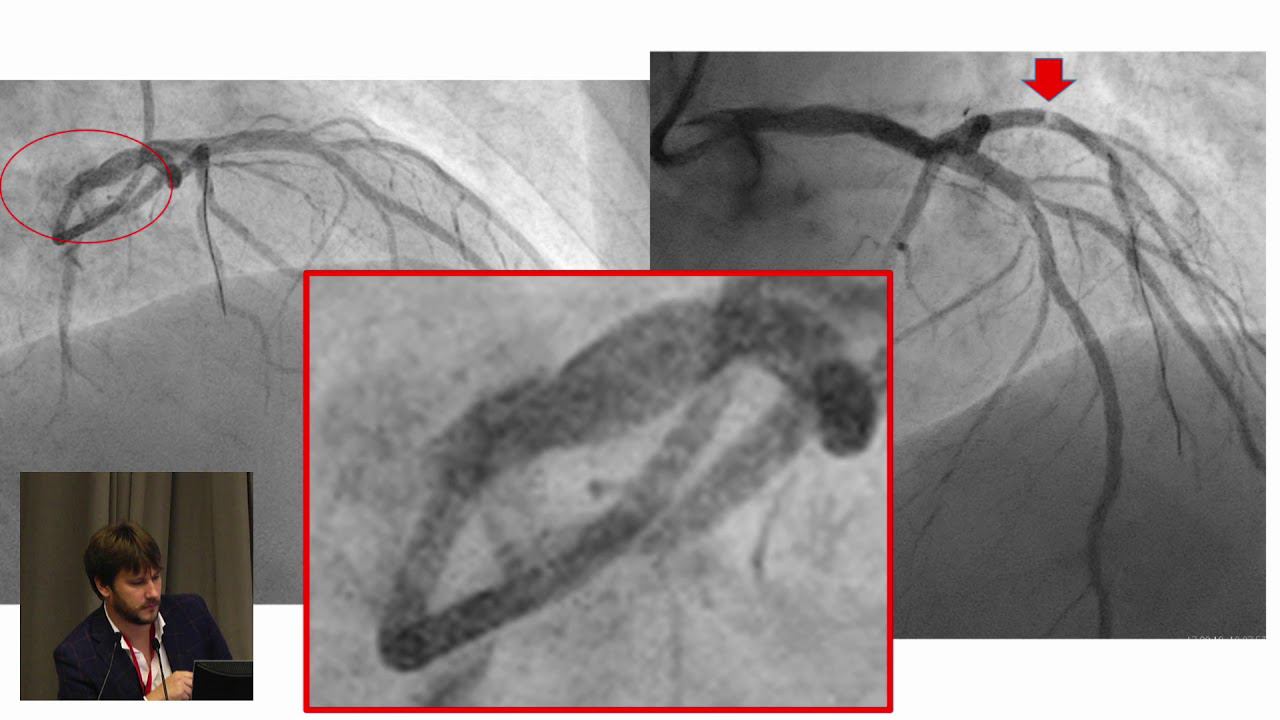

Коронография через руку

Коронография через руку 108 фотографий